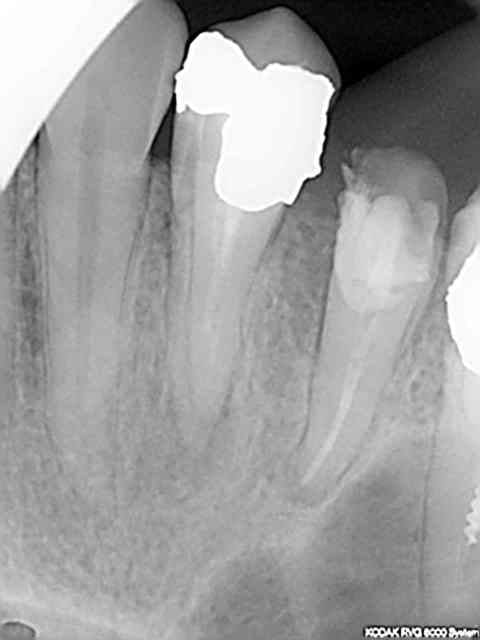

Ca c'est pas mal non plus en 45 mn, on se demande pourquoi thermo compacer au mac spadden et j'ai perdu un morceau de crochet au passage ! -)))))

Capture d e cran 2015 07 30 12.41 - Eugenol

Capture d e cran 2015 07 30 12.49 - Eugenol

Capture d e cran 2015 07 30 12.52 - Eugenol

Capture d e cran 2015 07 30 12.48 - Eugenol